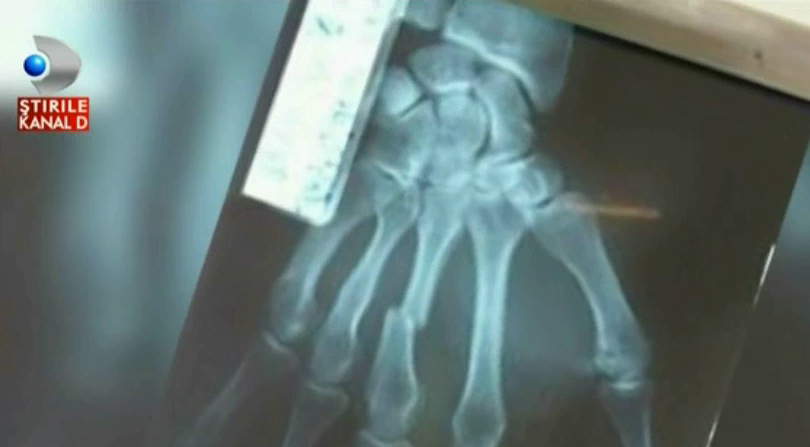

Dupa ce a ramas singur sa isi creasca fetita, Cornel Spiridon pare sa aiba ghinion in ultimul an. Dupa ce mama sa a trecut prin clipe grele dupa ce s-a imbolnavit grav, acesta are probleme la locul de munca. Din cauza unor clienti pusi pe scandal, barbatul a fost nevoit sa se apere si si-a fracturat mana in incaierare.